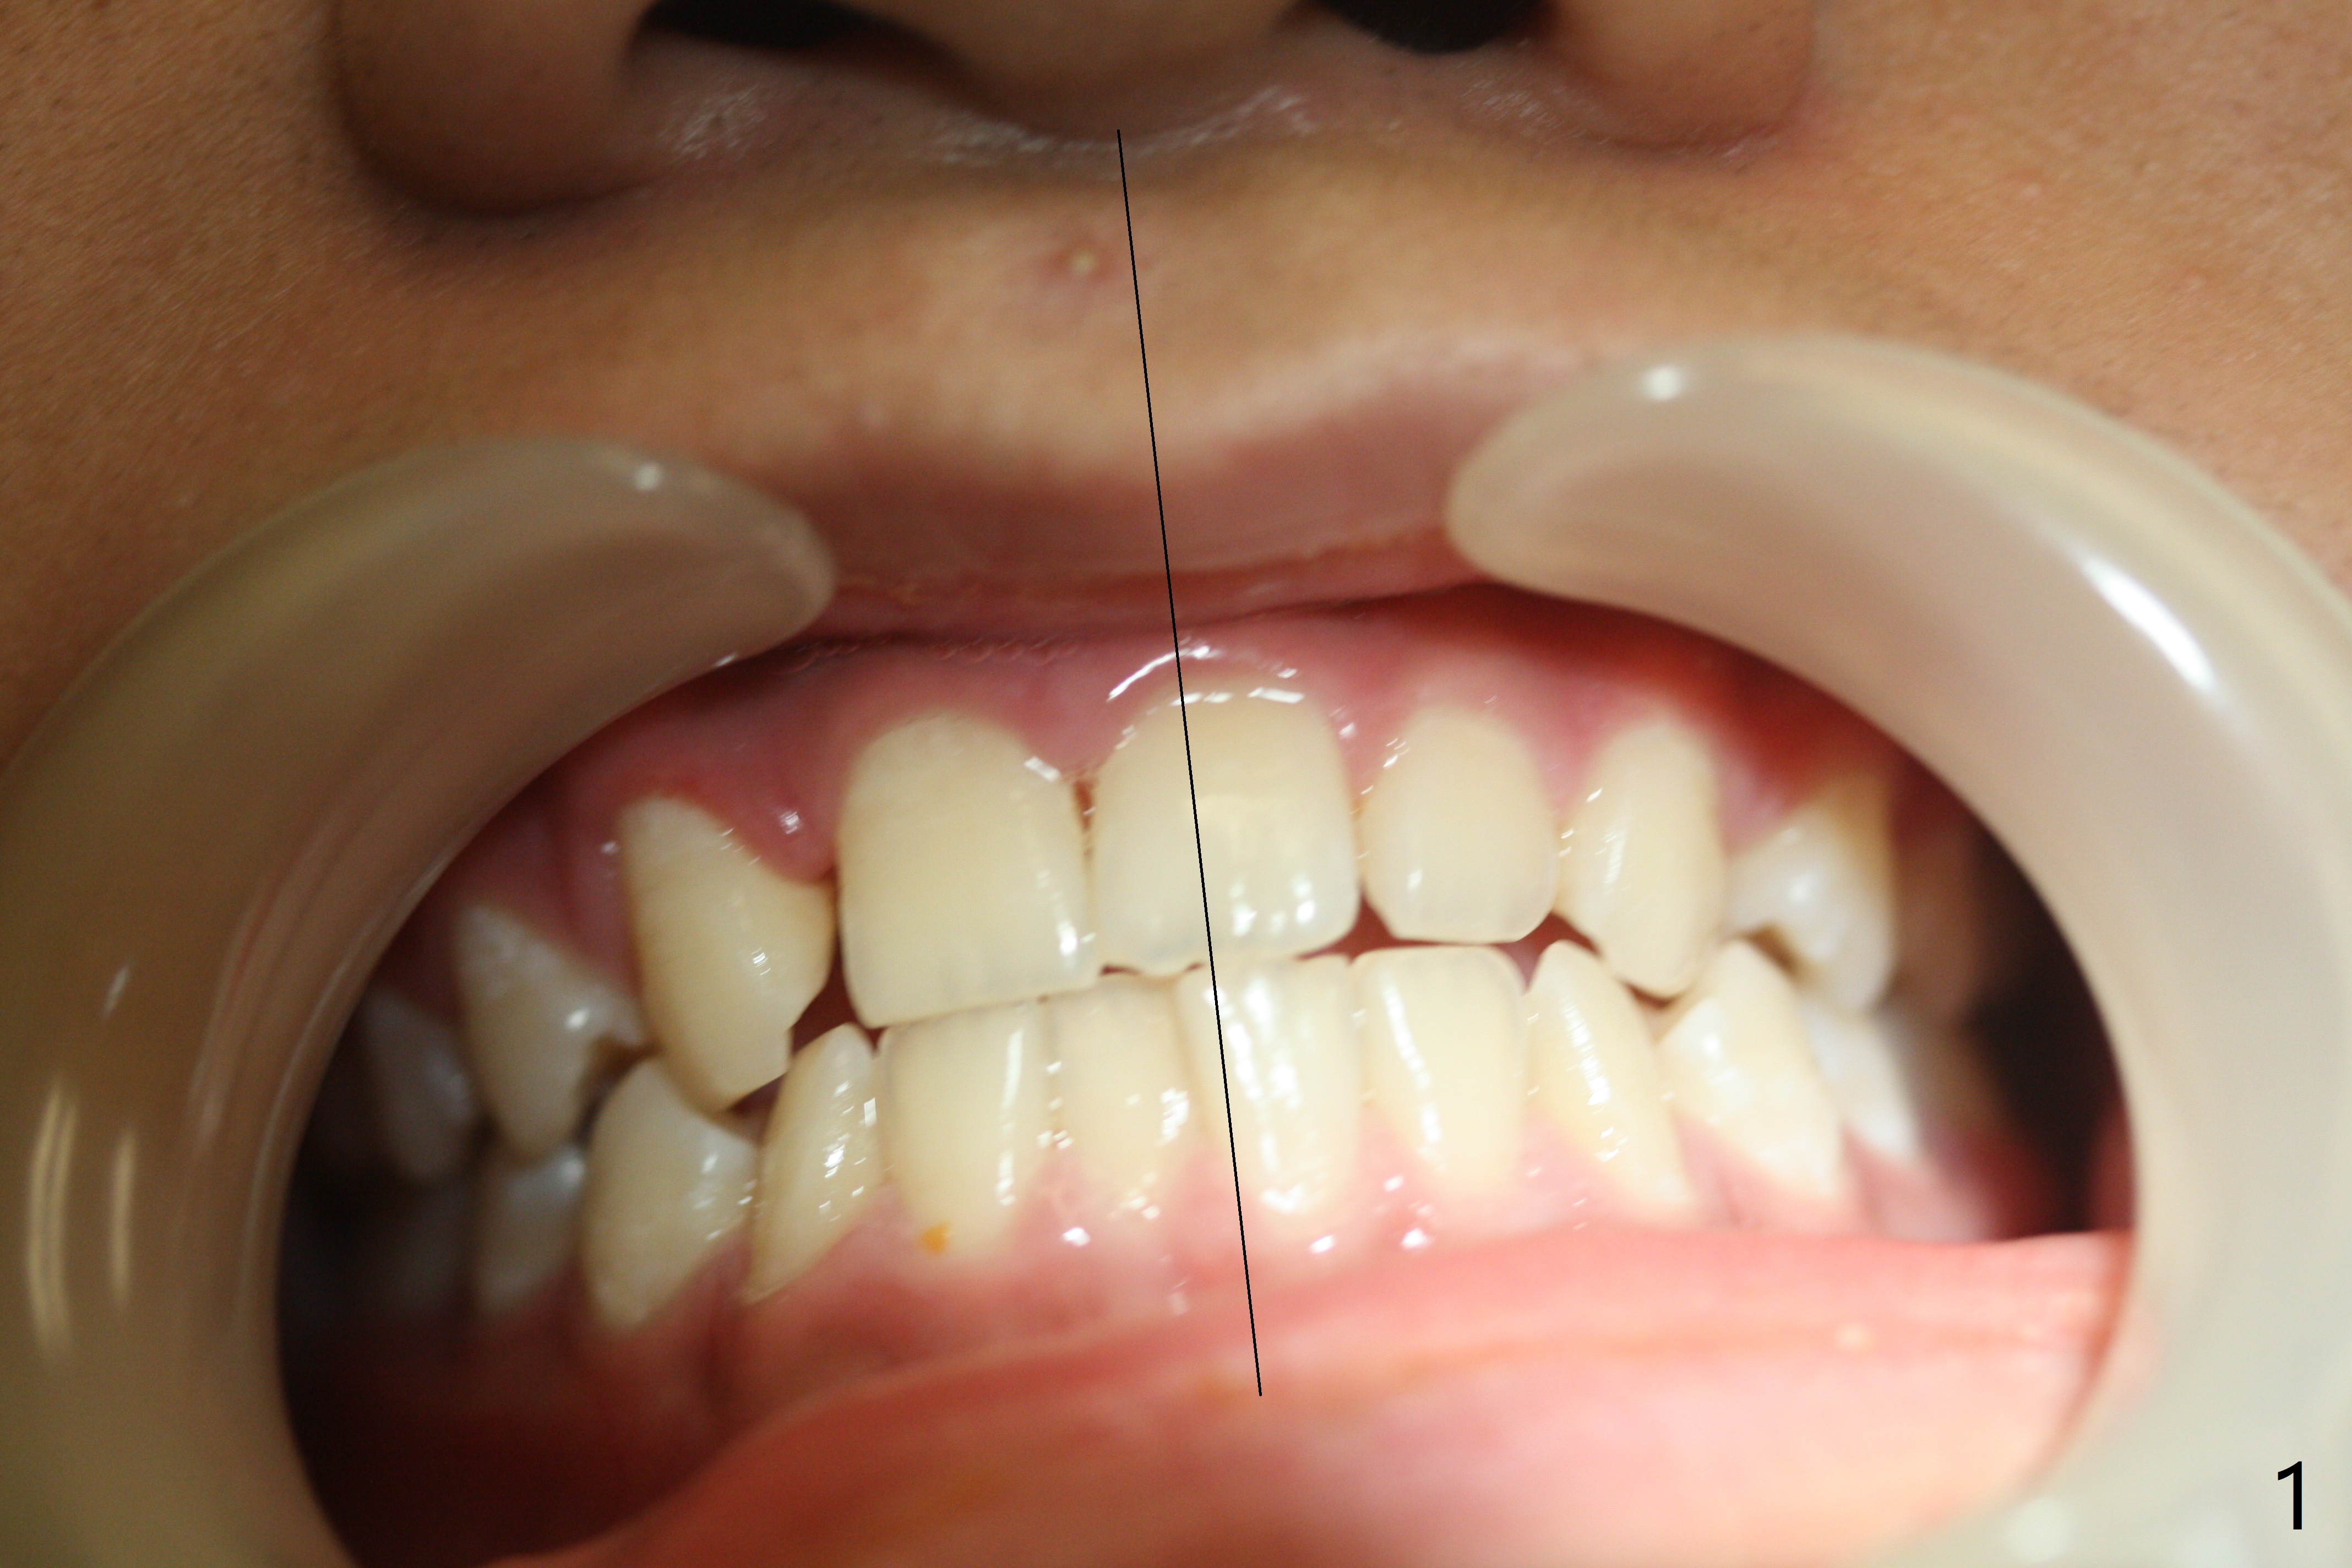

A 14-year-old man requests ortho because of crowding lower anterior and UR missing lateral (Fig.1-4). Open space for the future implant at UR2 will correct upper midline deviation (Fig.1) and change Class II malocclusion to I on the right (Fig.6, as compared to Fig.7). To control UR1,3 root torque, bracketing on these 2 teeth will be intentionally off (Fig.5). The treatment will take ~ 2 years. Prior to implantation at UR2, what type of prosthesis should be made?